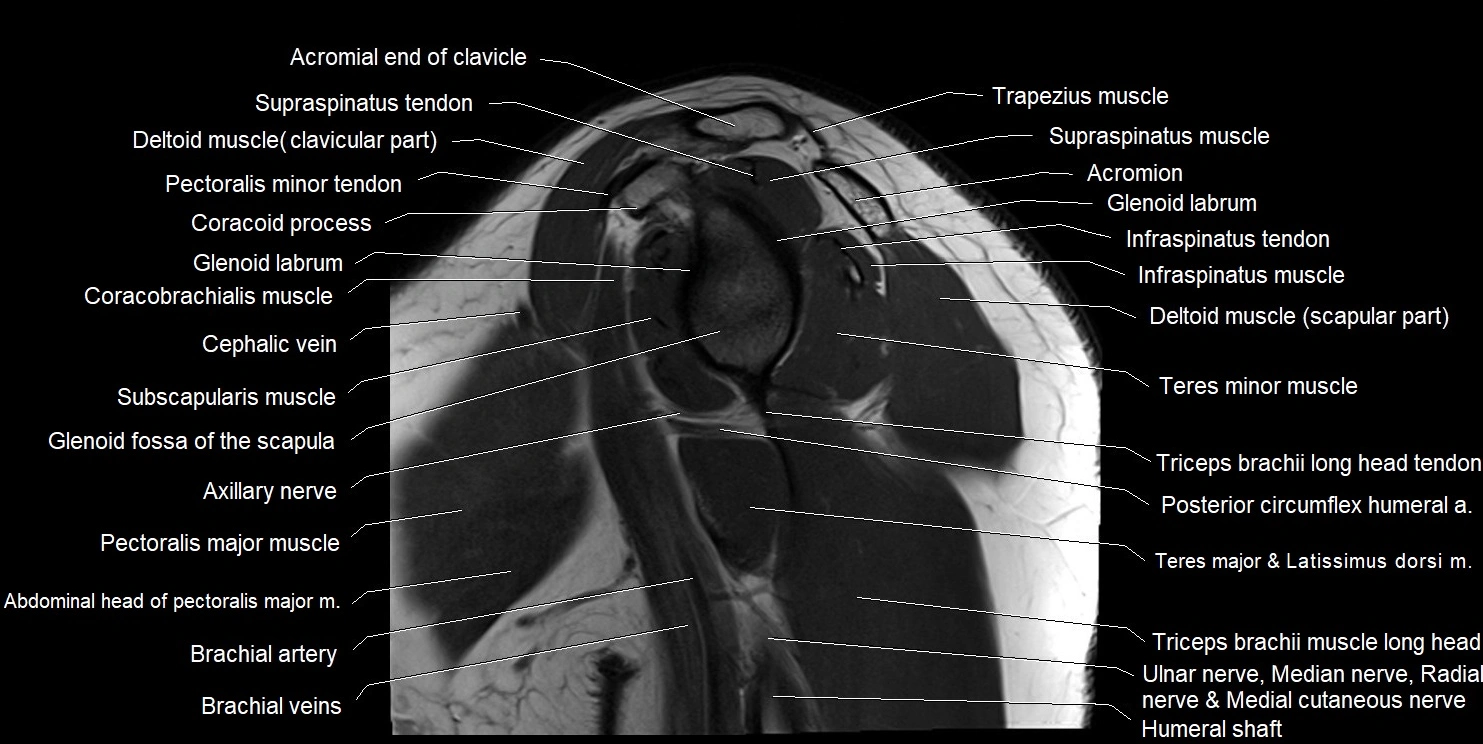

MRI images

image